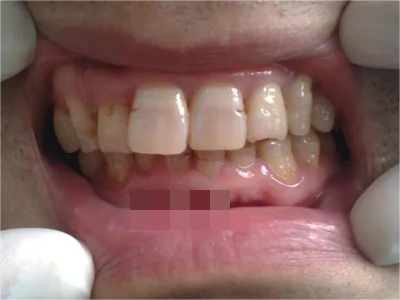

牙齿

小坑 · 缺损

牙釉质发育不全牙齿缺损有小坑图

重度牙釉质发育不全导致牙釉质表面呈棕褐色、棕黄色,其上有条状、窝状凹陷,并出现牙齿缺损,导致咬合关系破坏,也会出现对刺激敏感、疼痛等自觉症状。